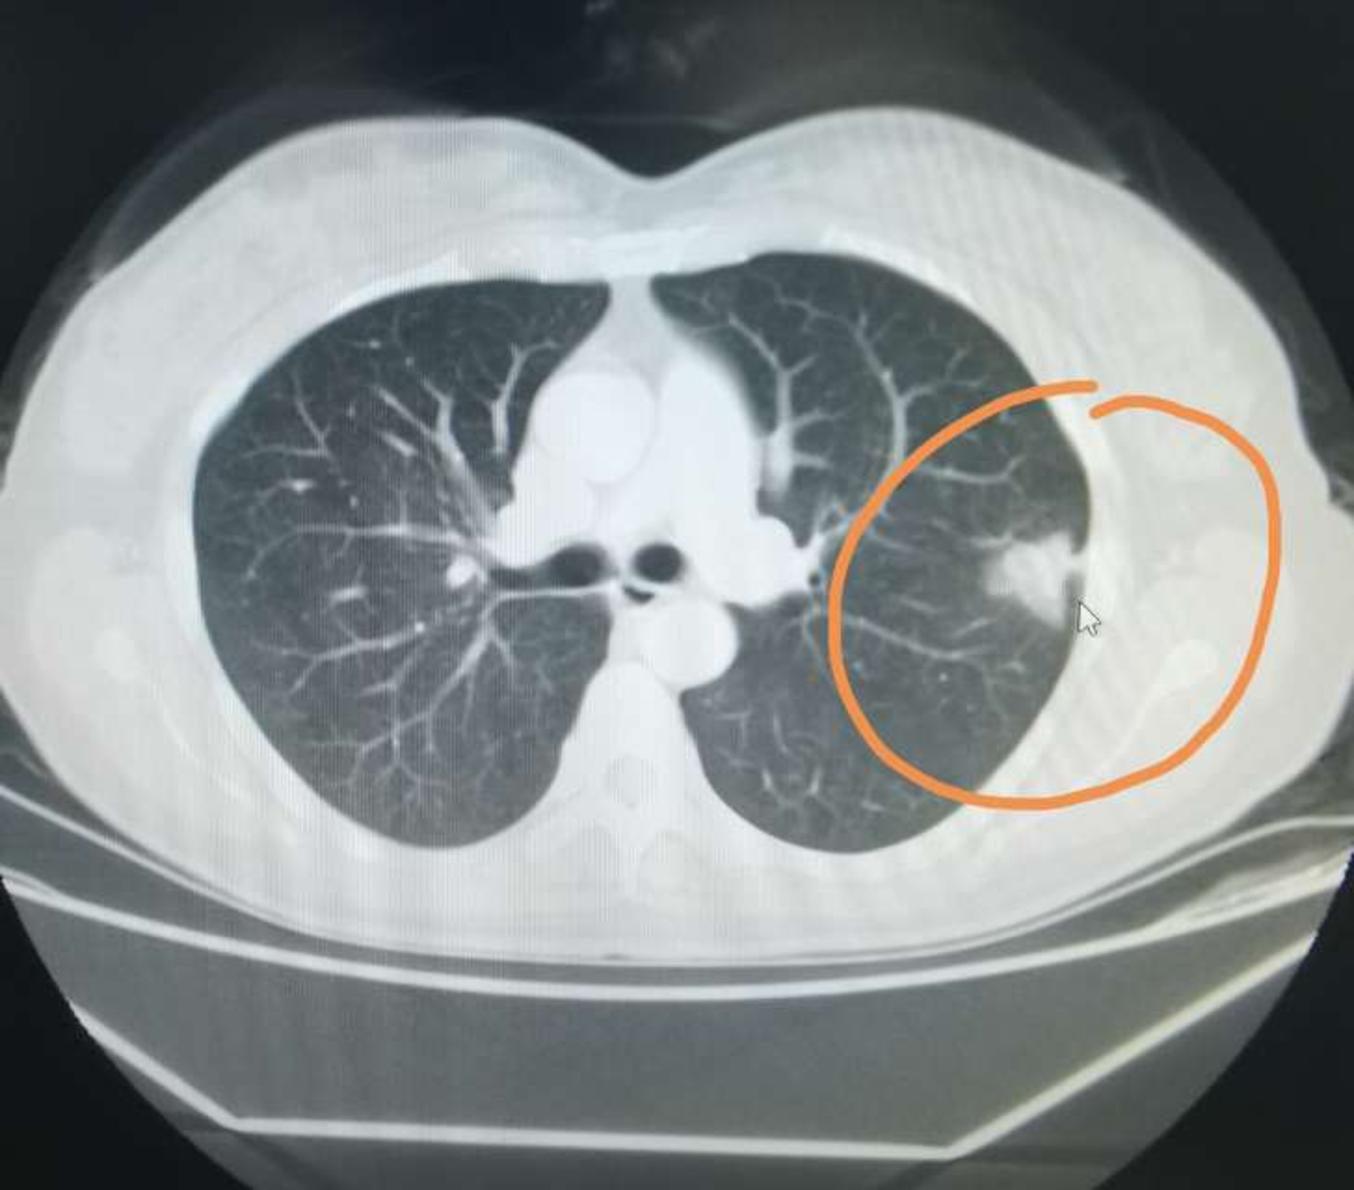

典型吸烟导致肺癌ct片,戒烟吧,烟民朋友